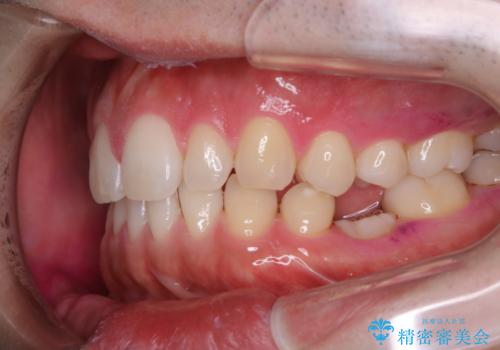

親知らずを抜いて1週間後にPMTC 歯のクリーニング

- 親知らずの抜歯後の約1週間後に抜糸(縫った部分の糸とり)で来院されました。その際、抜歯後は傷口が怖くて歯磨きが上手くできず、汚れや口臭が気になるためクリーニングも希望されました。

抜歯後は多少出血したり、違和感や痛みを感じたりすることがあります。そのため親知らずを抜いたり、外科的な処置をするといつも通りの歯磨きがしづらくなります。また、傷口の周りが心配で、歯ブラシをするのが怖くなるものです。抜歯後落ち着いたら、歯科医院にて専門の機械を使用しクリーニングをすることがおすすめです。抜歯前や後にPMTCを行うことで、お口の中の健康維持につながり、その後の感染・腫れ・口臭予防などになります。